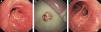

We report the case of a 65-year-old man with 2-month history of exertional dyspnea. Chest CT showed a mass in the left upper bronchus. Bronchoscopy revealed a possibly malignant, moruloid, highly vascularized, pink tumor partially obstructing the opening of the left lobar bronchus (Fig. 1A). When the surface of the tumor was lifted, a pediculated, hard, yellowish mass similar to popcorn was revealed. Attempts to remove the mass by forceps were unsuccessful, so cryotherapy was successfully used, with complete resection and resolution of the obstruction (Fig. 1B). There were no complications. Histopathological examination of the tumor confirmed the diagnosis of chondroma. A repeat bronchoscopy performed 8 weeks later showed an unobstructed left upper bronchus and normal bronchial mucosa at the site of resection (Fig. 1C).

Fig. 1.

Bronchoscopy image of a moruloid, highly vascularized, pink tumor (A), resected to reveal a hard popcorn-like mass (B), unobstructed left upper bronchus and normal bronchial mucosa at the site of resection (C).